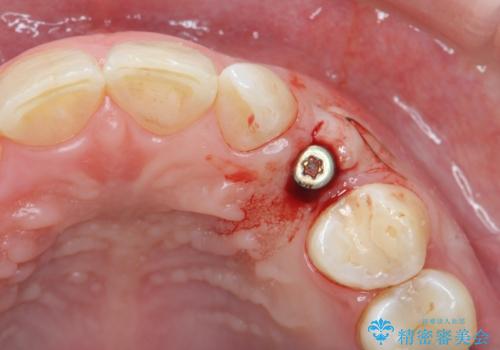

骨造成を伴う 前歯部インプラント治療

- 欠損している前歯のインプラント治療を希望され来院されました。

適切なインプラント埋入を行い、不足している骨量を補うため骨の造成を併用したインプラント治療を計画します。

前歯のインプラント治療は骨量・歯肉の厚み・インプラントの方向をしっかりと計画することで、審美的で長持ちを期待できるような仕上がりとなります。